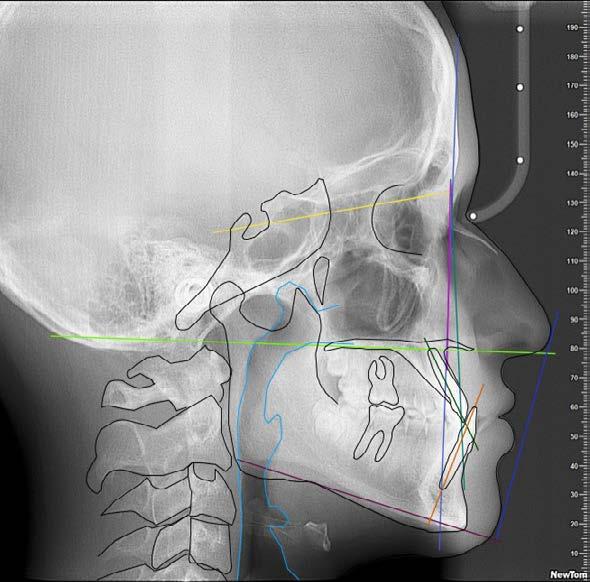

Figura 1. Perfil de inicio. Figura 2. Cefálica lateral.

Se presenta un paciente en edad de 15 años y 2 meses. Refiere que acude a consulta por evaluación. En la valoración extraoral presente la hiperdivergencia y sus posiciones dentales (Figura 1), tiene un perfil convexo con hiperactividad del músculo mentoniano e incompetencia labial, y en la radiografía lateral de cráneo inicial (Figura 2) se aprecia el patrón esquelético clase II severo.

En la sobreimposición del componente craneofacial inicio (color negro) y final (color rojo), se observa un paciente con crecimiento, con cambio a nivel de los labios superior e inferior. Con rotación mandibular hacia adelante y hacia arriba, debido a la Lefort I con impactación de 4 mm. El avance mandibular de 9 mm y la mentoplastía de avance de 4 mm (Figura 17).